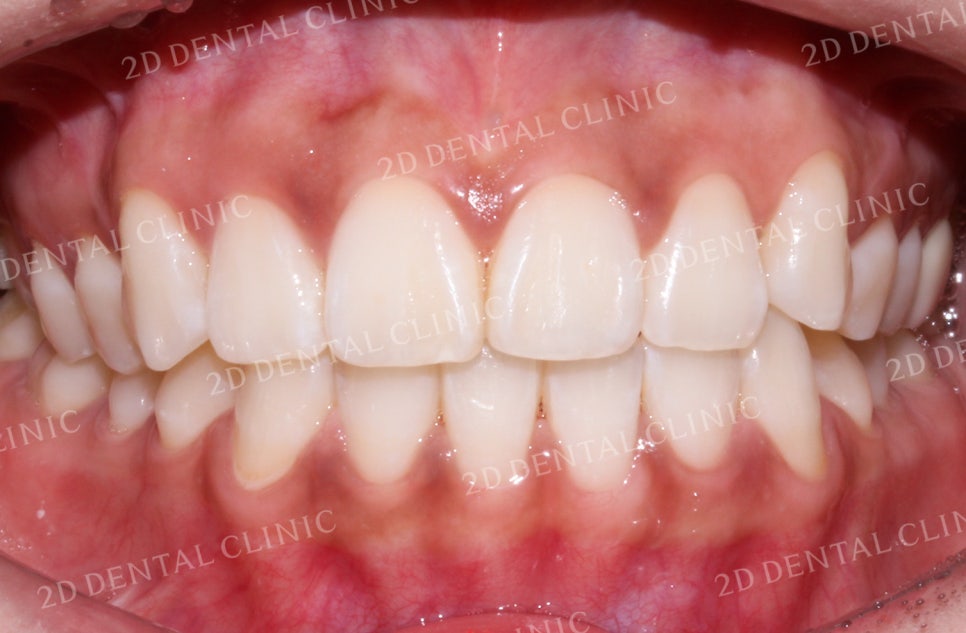

돌출입 교정 후 전치부의 사진입니다.

앞니가 바깥으로 뻐드러지게 나와있던

교정 전과 비교하여 교정 후 앞니가

부드러운 곡선으로 배열된 모습이네요.

상하악 전치부에서

발견되었던 크라우딩도

약 10개월의 교정치료 후

고르게 바뀌었습니다.